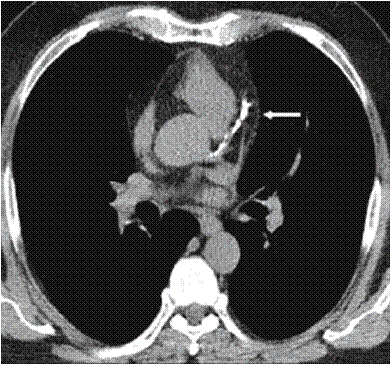

el signo de la arteria basilar hiperdensa que es visible en la TC simple. En los pacientes con

sospecha de ictus isquémico vertebrobasilar, la presencia del signo de la

basilar hiperdensa se asocia a la existencia de una oclusión aguda de la

arteria basilar confirmada mediante angio-TC con una especificidad (98%) y

sensibilidad (71%) elevadas.

- La lesión esta localizado el la arteria basilar, dando el clásico “signo de la arteria basilar hiperdensa”, visible en nuestro estudio en los cortes axiales y reconstrucciones coronal y sagital, lo cual traduce éstasis vascular por trombosis.